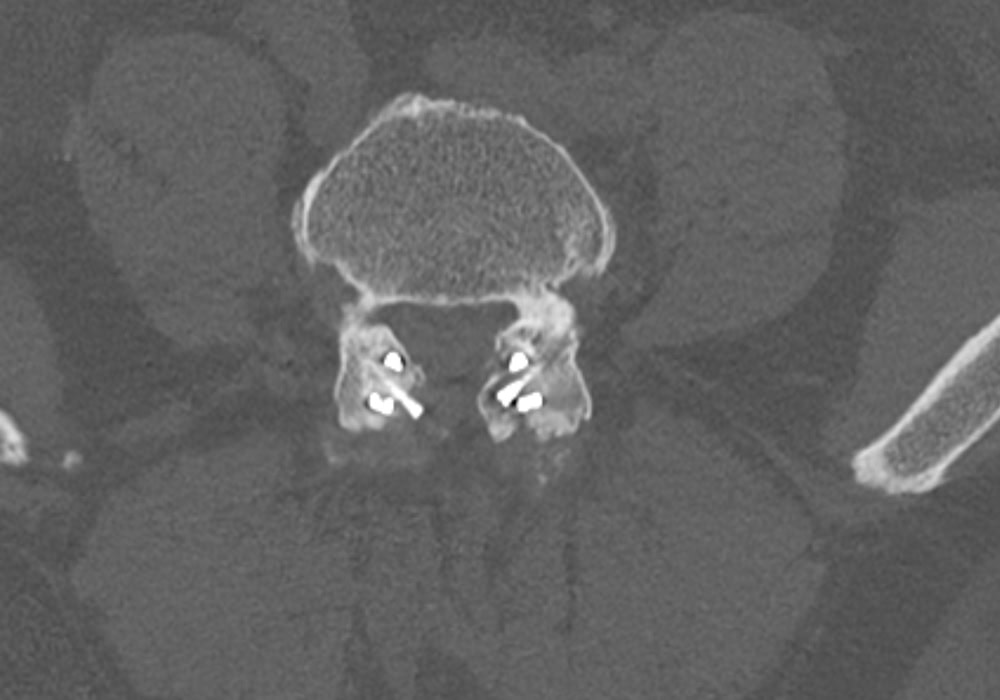

Preop.

2-Year Postop

2-year Postop.